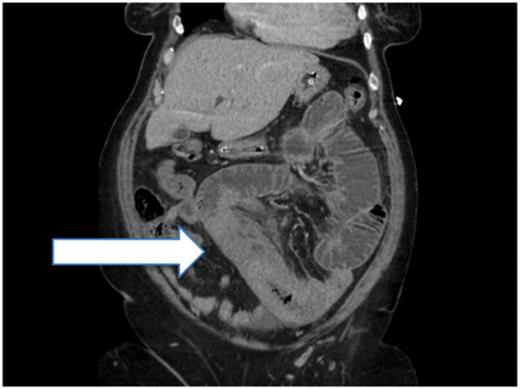

The following morning on the post-take ward round he was peritonitic and a decision was made to take him for an exploratory laparotomy prior to further imaging. An INR was sent as a work-up for theatre, which returned at 12.6; drug reconciliation revealed that he was on warfarin. Berriplex was used to normalize his clotting prior to theatre on advice from haematology.

Intraoperatively, there was a 30-cm segment of proximal jejunum with spontaneous intramural haemorrhage; the bowel was viable with pulsatile vessels in the mesentery. There was no intraluminal bleeding or any other cause for obstruction; therefore, washout and closure was performed without resection. Postoperatively, he recovered well and was discharged on Clexane, with the view to restarting warfarin in the community.